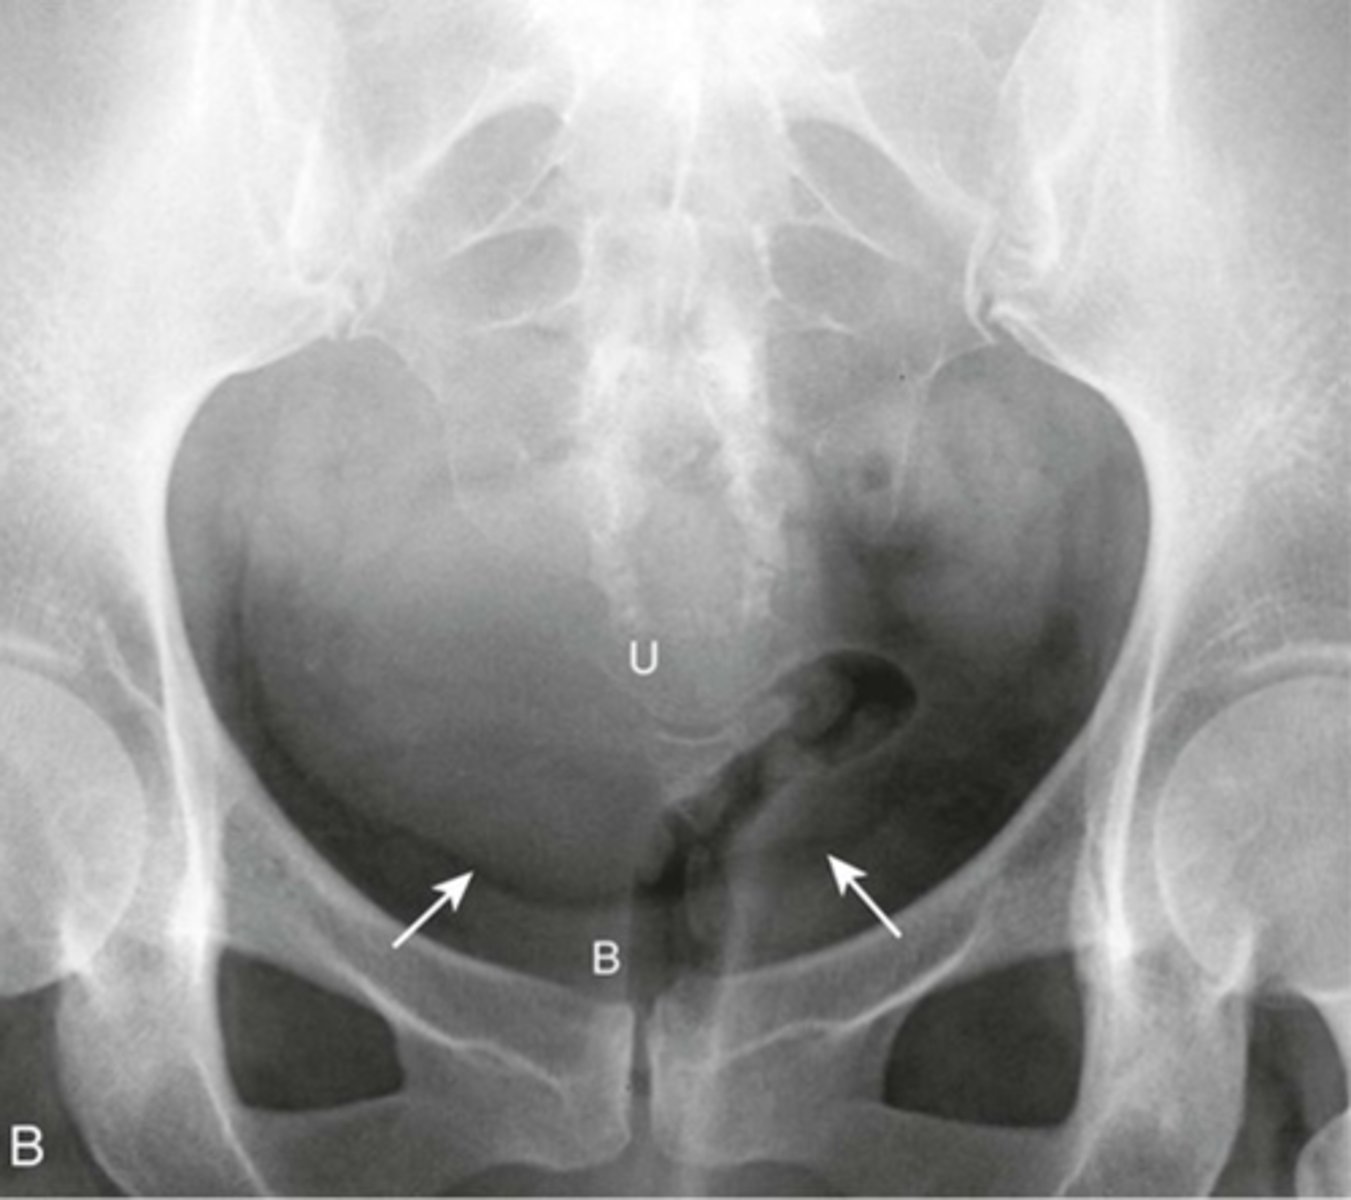

ENLARGED UTERUS

U: enlarged uterus

(can be distinguished from bladder because there is a FAT PLANE between it and urinary bladder)

WHITE ARROWS: fat plane

B: Urinary bladder